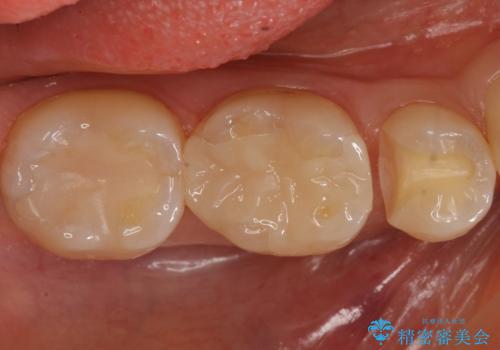

歯と歯の間の虫歯 セラミックインレーでの治療

- 矯正後の検査で歯と歯の間の虫歯が確認された患者様です。

虫歯の除去後、セラミックインレーで修復していきます。

レントゲン画像からは読み取りづらいですが、視診にて歯の一部が黒く透けているのが確認できました。

小さな虫歯でも見落とさずに精度の良い修復をすることで二次う蝕のリスクを減らすことができます。